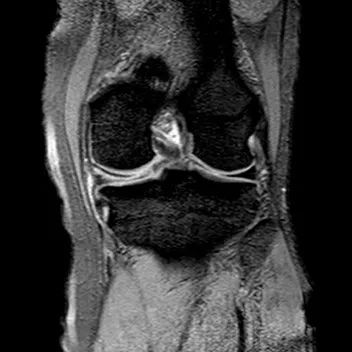

1、宽度减小,在通过半月板体部的冠状面上蝶形消失,同时可见内移的半月板位于髁间窝、交叉韧带旁2、矢状面示残余的前角或后角变小或截断3、半月板前(后)角增宽或双半月板前(后)角征4、双前交叉韧带或双后交叉韧带征

桶柄状撕裂:宽度减小,在通过半月板体部的冠状面上蝶形消失,同时可见内移的半月板位于髁间窝、交叉韧带旁